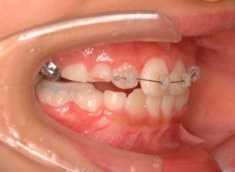

治療開始から6ヶ月で反対咬合の解消は達成されておりますが、これで治ったわけではなく、上顎の劣成長を改善しなければならないので、ここからしっかりとフェイスマスクを使用していただきます。

治療開始から6ヶ月後